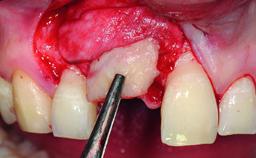

A 32-year-old female Caucasian patient with a compromised maxillary right central incisor was referred to us by a general dentist. Her chief complaints were discomfort and mobility of tooth 11 with unsatisfactory esthetics due to discoloration. The patient reported a previous trauma, some years earlier, as the origin of pathology on the afflicted tooth. Anamnesis was negative for any other dental or periodontal pathology in the remaining dentition. The patient did not take any medication and reported to be a light smoker (5–10 cigs/day). She had high esthetic expectations of her treatment. The extraoral examination revealed a high smile line with full exposure of her maxillary teeth and surrounding soft tissue in the area between the second premolars.

Defining Characteristics One missing tooth to be replaced by an implant-borne prosthesis

Placement Protocol Early or late implant placement

Bone Volume Deficient horizontally, requiring prior grafting

Esthetic Risk High